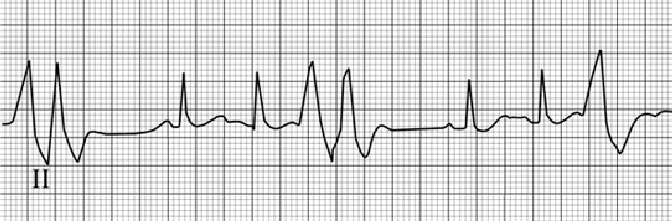

This rhythm strip shows sinus tachycardia with premature ventricular complexes. The underlying sinus tachycardia is reflected by normal P waves preceding each sinus QRS at a rate greater than 100 per minute. Here the rate is approximately 120 beats per minute. The earlier premature ventricular complexes are wide and different from the sinus QRS and are not preceded by a premature P wave. Some are occurring in pairs, or couplets. The significance of isolated and paired ventricular complexes is determined by the clinical setting in which they occur.